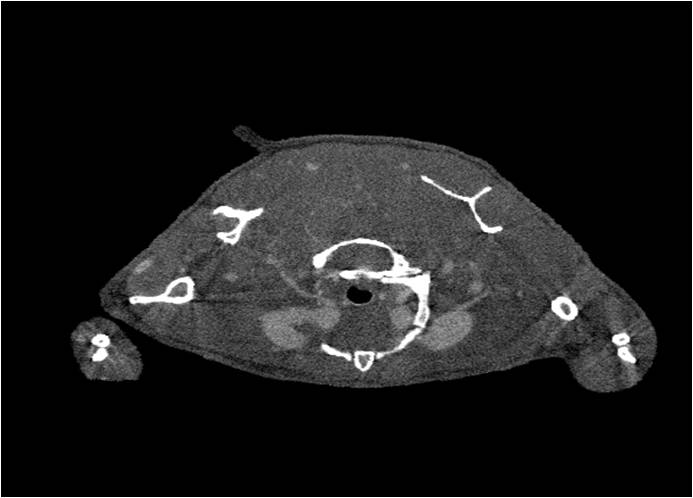

檢測案例

小鼠股骨

超高分辨率模式下像素大小為9μm。

A軸向和矢狀面顯示小鼠股骨結構。

B用鈦材料植入的穿過骨頭的冠狀切片